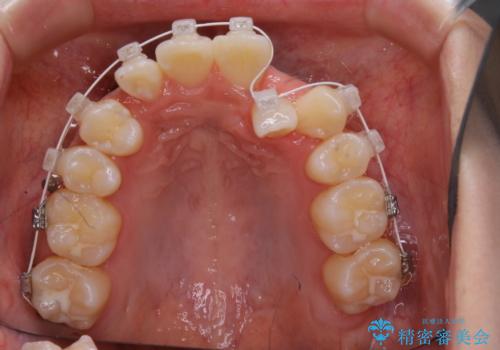

- 矯正装置

- ワイヤー矯正 審美装置

当初、犬歯が動くようであれば代わりに小臼歯を抜歯する予定でしたが、

開窓して器具で力をかけても動く様子がなかったため抜歯とし、小臼歯を犬歯に見立てて治療を完了しました。

結果的に見た目の違和感もなく、期間の短縮にもつながりました。

今回のように不確定要素がある治療の場合、ワイヤー治療なら臨機応変に対応することが可能となります。